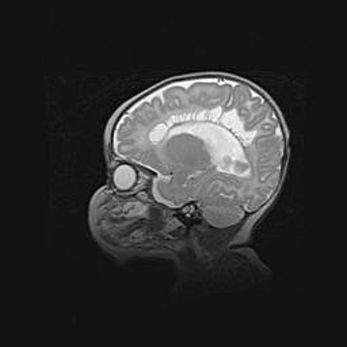

Аномалия Денди-Уокера. Признаки гипоплазии мозолистого тела.

Возраст: 5 месяцев 3 дня

Вес: 5550 г

Пол: мужской

Окружность головы: 39 см

Срок гестации: 40 недель

Аномалия Денди-Уокера – это порок развития головного мозга, для которого характерна триада симптомов: гипотрофия или аплазия червя мозжечка и/или полушарий мозжечка, расширение четвёртого желудочка с формированием ликворной кисты задней черепной ямки, гипертензионная гидроцефалия различной степени.

Гипоплазия мозолистого тела относится к дефектам внутриутробного этапа развития мозговой ткани, возникающим в процессе закладки структур головного мозга, что происходит на начальных этапах развития эмбриона.